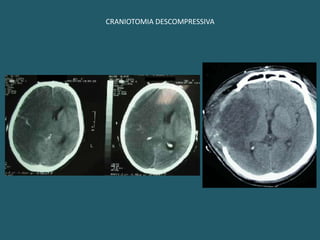

CIRURGIAS DESCOMPRESSIVASHidrocefalias